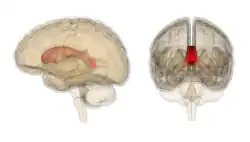

Corpus callosum from above, front part at the top of the image

Sagittal section of a brain, front part to the left. The corpus callosum can be seen in the center, in light gray

The corpus callosum (Latin for "tough body"), also callosal commissure, is a wide, thick nerve tract, consisting of a flat bundle of commissural fibers, beneath the cerebral cortex in the brain. The corpus callosum is only found in placental mammals.[1] It spans part of the longitudinal fissure, connecting the left and right cerebral hemispheres, enabling communication between them. It is the largest white matter structure in the human brain, about 10 cm (3.9 in) in length and consisting of 200–300 million axonal projections.[2][3]

A number of separate nerve tracts, classed as subregions of the corpus callosum, connect different parts of the hemispheres. The main ones are known as the genu, the rostrum, the trunk or body, and the splenium.[4]

The corpus callosum forms the floor of the longitudinal fissure that separates the two cerebral hemispheres. Part of the corpus callosum forms the roof of the lateral ventricles.[5]

The corpus callosum has four main parts – individual nerve tracts that connect different parts of the hemispheres. These are the rostrum, the genu, the trunk or body, and the splenium.[4] Fibres from the trunk and the splenium, known together as the tapetum ("carpet"), form the roof of each lateral ventricle.[6]

The front part of the corpus callosum, towards the frontal lobes, is called the genu ("knee"). The genu curves downward and backward in front of the septum pellucidum, diminishing greatly in thickness. The lower, much thinner part is the rostrum and is connected below with the lamina terminalis, which stretches from the interventricular foramina to the recess at the base of the optic stalk. The rostrum is named for its resemblance to a bird's beak.

The end part of the corpus callosum, towards the cerebellum, is called the splenium. This is the thickest part, and overlaps the tela choroidea of the third ventricle and the midbrain, and ends in a thick, convex, free border. Splenium translates as "bandage" in Greek.

The trunk of the corpus callosum lies between the splenium and the genu.